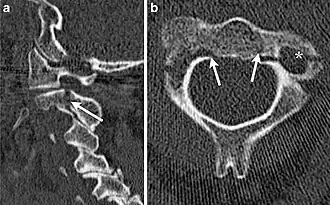

| Tomografia computadorizada apresenta uma fratura do enforcado | |